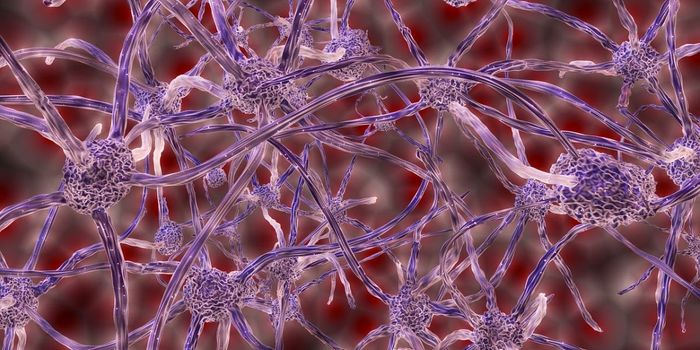

FEB 17, 2025NeuroscienceResearchers have discovered a new type of neuron that plays a critical role in recognition memory.

FEB 11, 2025NeuroscienceA study published in Science Signaling on the neural circuitry mediating addiction has made significant strides, particu ...